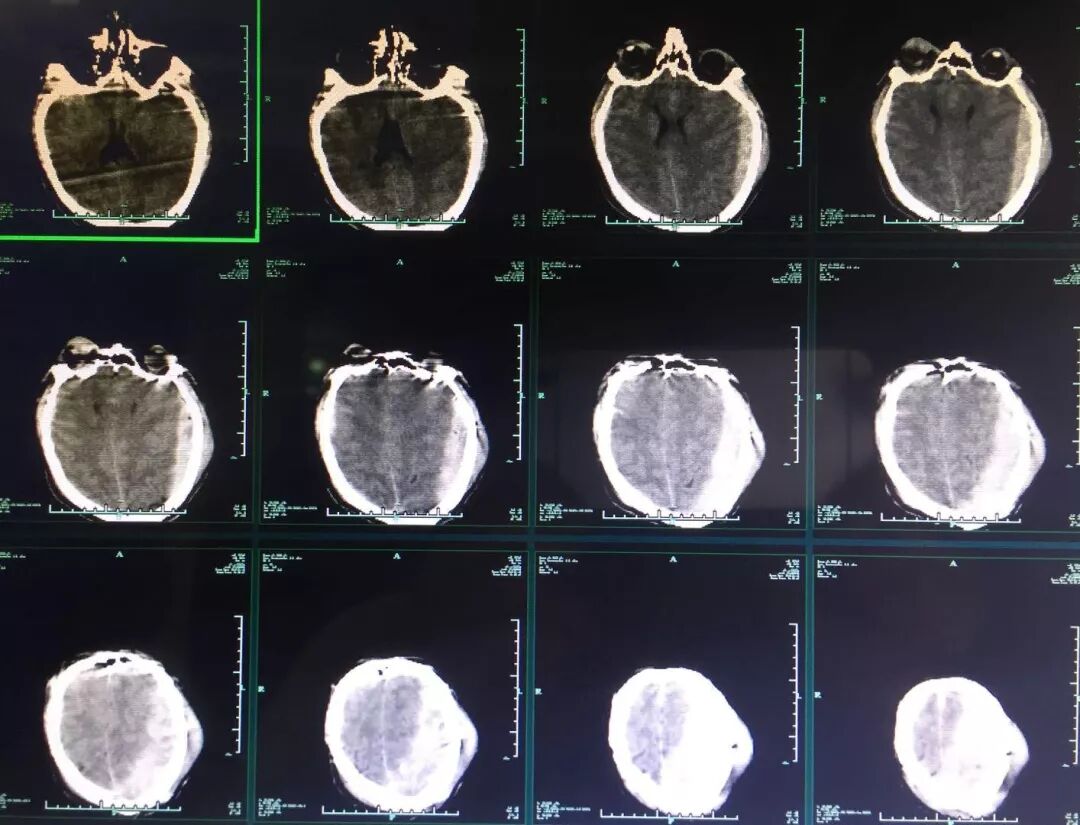

入院时患者深昏迷,GCS6分,左侧瞳孔0.5cm,右侧瞳孔0.3cm,对光反射均消失。急诊头颅CT提示:“左侧额颞顶部急性硬膜外血肿,脑疝(图1)”,急诊行左侧颅内血肿清除+去骨瓣减压术,术后即刻头颅CT复查提示:“右侧额颞叶急性硬膜下血肿”(图2),再次开颅行右侧颅内血肿清除+去骨瓣减压术。术后转ICU科呼吸支持治疗。术后再次复查CT,见血肿已清除,无硬膜下积液,中线基本居中(图3)。术后5天患者病情好转,GCS8分,双侧瞳孔0.3cm,对光反射迟钝,转回神经外科监护病房。

图1. 急诊头颅CT提示:左侧额颞顶部急性硬膜外血肿。